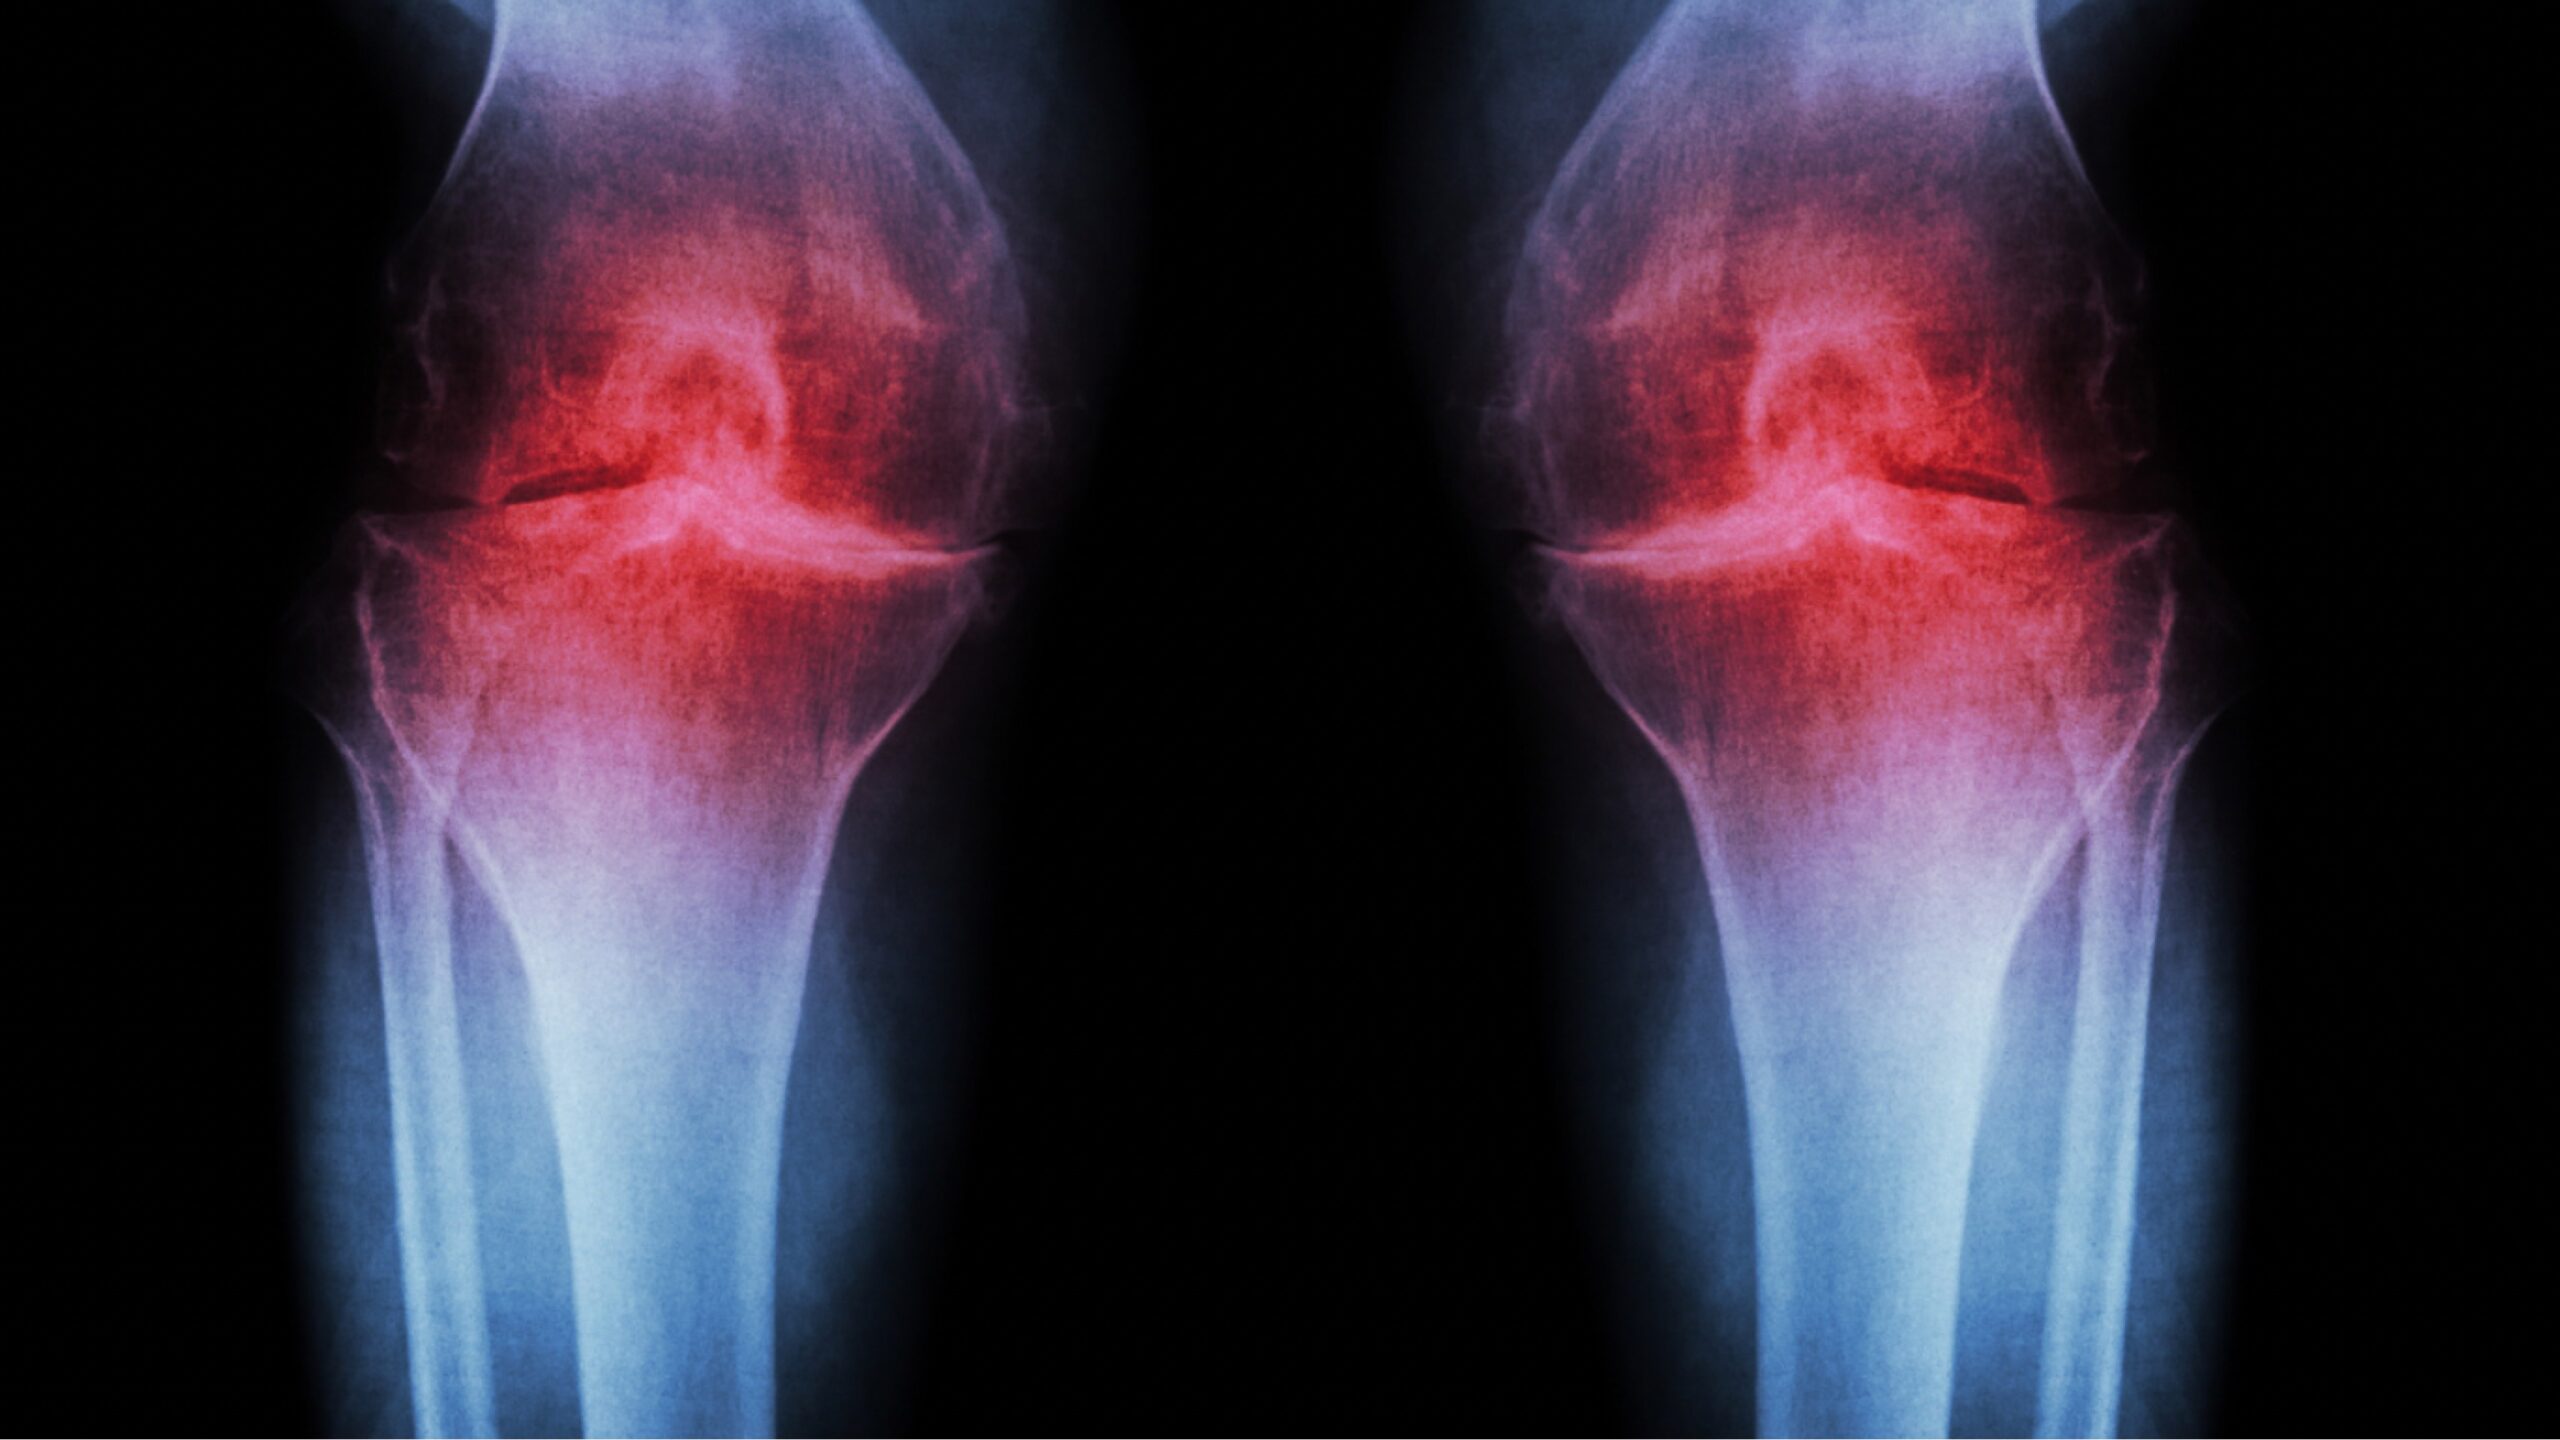

Arthrose ist eine chronische Gelenkerkrankung, bei der die schützende Knorpelschicht im Gelenk nach und nach abgebaut wird. In der Folge reiben Knochen aufeinander, es kommt zu Schmerzen, Entzündungen und Bewegungseinschränkungen.

Betroffen sind oft die Knie, Hüften, Finger, Schultern oder die Wirbelsäule. Doch trotz dieser Einschränkungen gilt: Je aktiver Sie bleiben, desto mehr Lebensqualität können Sie sich bewahren.